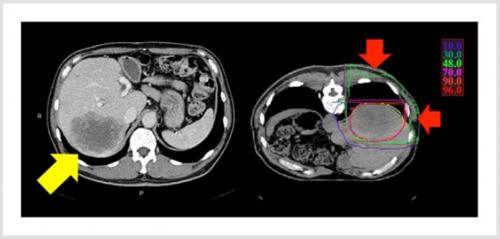

図1 典型的な肝腫瘍に対する重粒子線治療の放射線線量分布(例は大腸がん肝転移)

正常な肝臓には照射されないため、大きな腫瘍でも肝機能を維持できます※6。